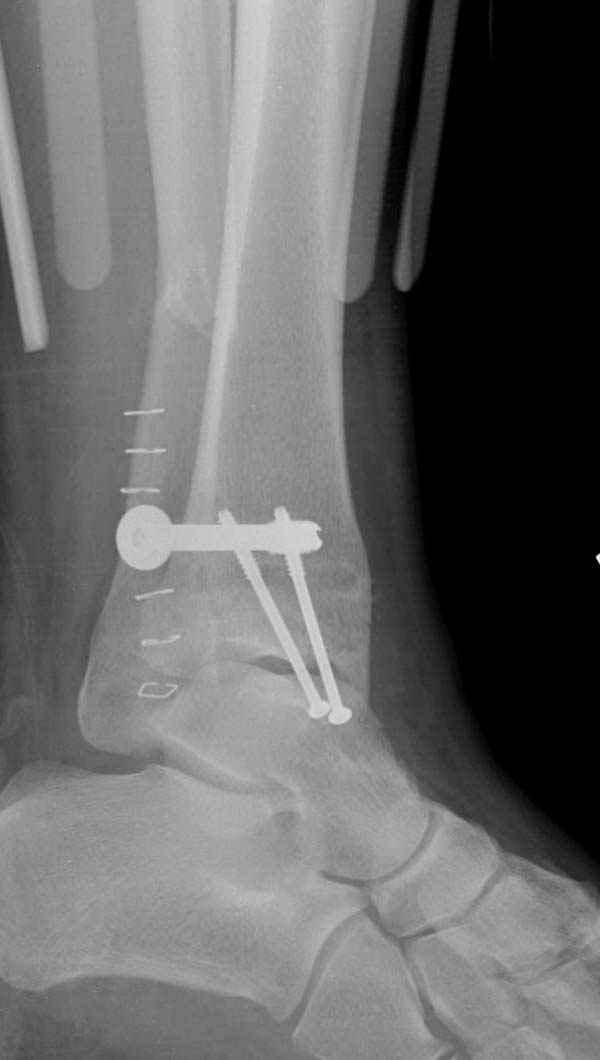

Ниже рентгенограммы

До операции 28 июля

Операция 29 июля

Через месяц

Боковой через месяц

15 ноября прямой

15 ноября боковой

15 ноября трехчетвертной

12 января прямой

12 января боковой

12 января трехчетвертной

Риторический вопрос - в каком руководстве рекомендован такой способ остеосинтеза наружной лодыжки?

Очевидно, такой результат операции был запрограммирован. При невосстановленной длине и практически нефиксированной малоберцовой кости (этот кортикальный винт - как карандаш в стакане), при неустраненном подвывихе, невправленной и тоже нефиксированной внутренней лодыжке нет стабильной вилки сустава. Если такую операцию сделать даже сразу, а не через 4 месяца, то результат ожидаем

тот же.

Вообще говоря, такое повреждение вполне успешно можно лечить без операции - если 6 недель подержать в гипсовом "сапожке" с хорошо устраненным подвывихом. Вероятное несращение внутренней лодыжки не обязательно компрометирует результат.

Ну а уж если выбран остеосинтез - нначать надо было с репозиции малоберцовой кости с точным восстановлением длины, с фиксацией треть-трубчатой пластиной по задней поверхности. Позиционный винт

избыточен - повреждение практически подсиндесмозное. А если бы

действительно было повреждение синдесмоза - в 4 месяца позиционный винт - не решение. Внутренню лодыжку такую - надо было бы спицами и проволочной петлей. Извините за эти банальности.

Вариант с артродезом уже обсудили. Хотя, после увиденых снимков, пессимизм насчет восстановительной операции у меня, например, несколько уменьшился. Особенного уж какого-то остеопороза не видно даже на январских снимках. Можно черед мини-доступы убрать винты, аппаратом вправить малоберцовую кость, устранить подвывих стопы. Ну а дальше фиксировать малоберцовую пластиной сзади. А может, и напряженной Y-спицей попробовать - Анатолий Федорович, как Вы полагаете? Внутреннюю - то, что осталось, если уже не получится сделать спицами и проволокой, то что-то типа пластики дельтовидной связки. А может, и не трогать ее вовсе... В общем, выбор непростой,

много факторов надо взвесить.